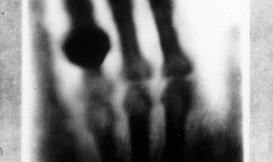

倫琴除了獲得1901 年的諾貝爾物理獎之外,符茲堡大學更頒授榮譽醫學博士給倫琴。今天醫學界稱倫琴為影像診斷學之父,無數病人因為他的物理研究而得救。